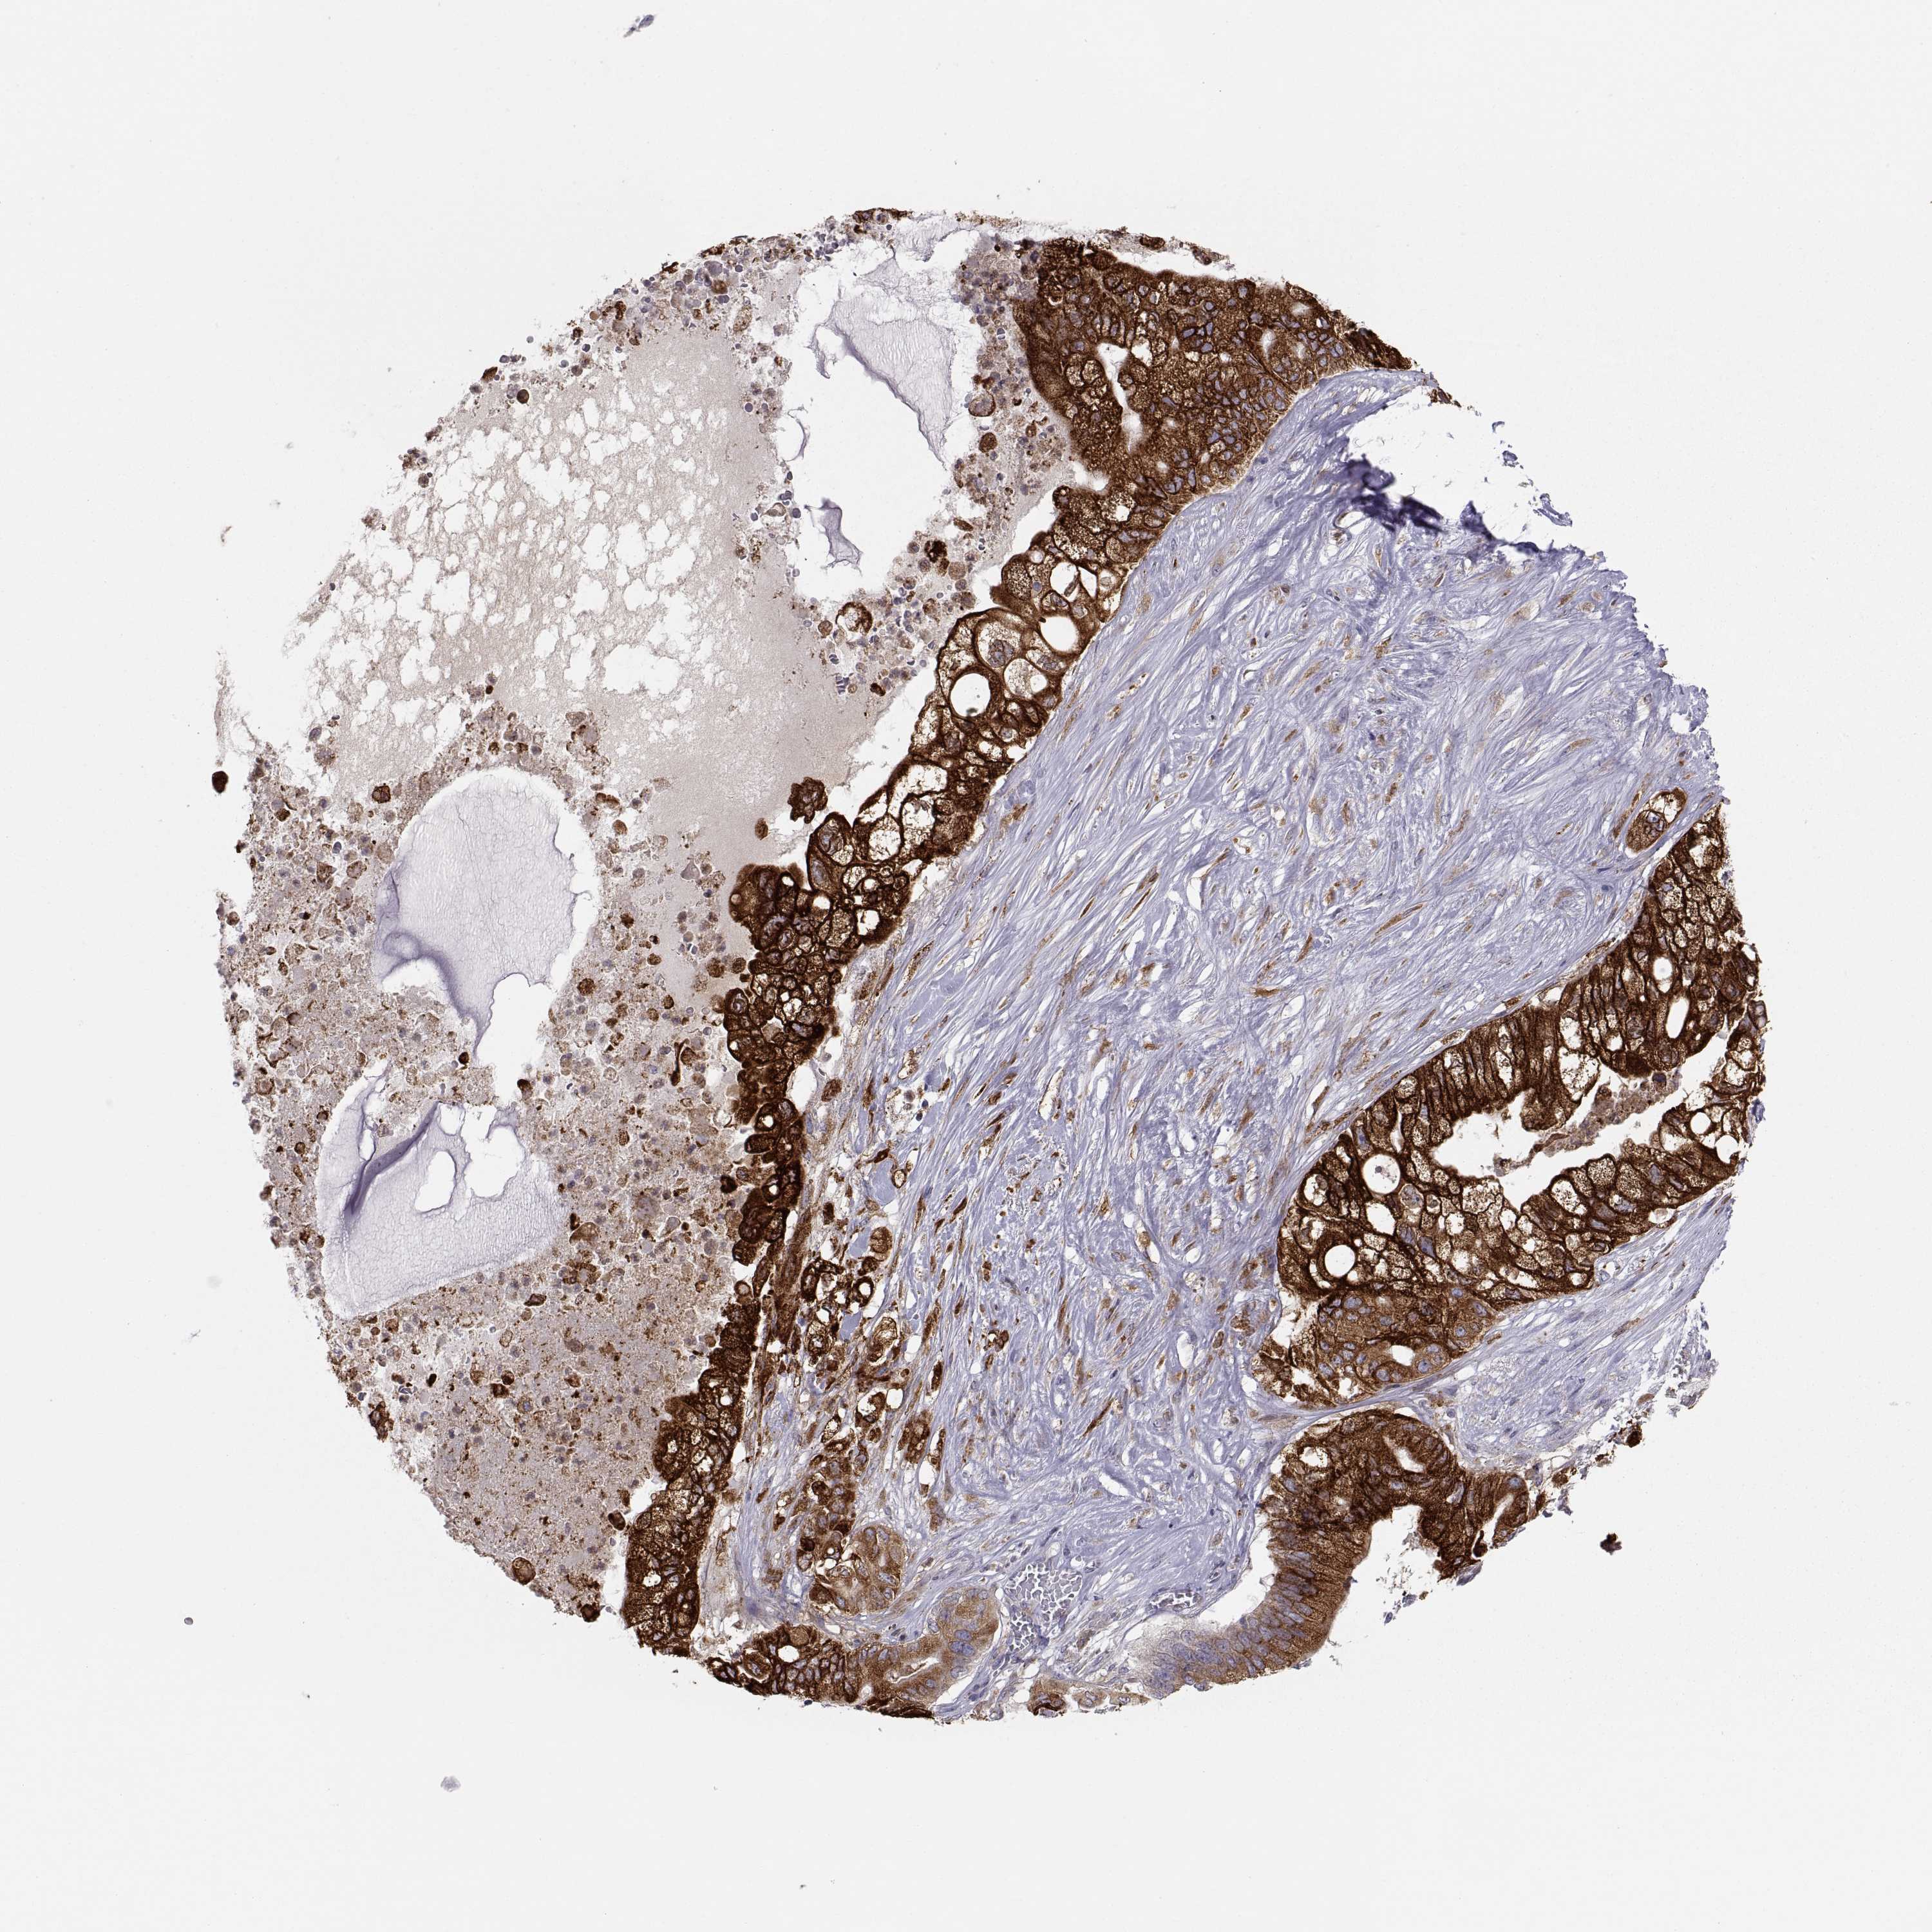

PANCREATIC CANCER - Protein expressioni

A mouse-over function shows sample information and annotation data. Click on an image to view it in a full screen mode. Samples can be filtered based on level of antibody staining by selecting one or several of the following categories: high, medium, low and not detected. The assay and annotation is described here.

Note that samples used for immunohistochemistry by the Human Protein Atlas do not correspond to samples in the TCGA dataset.

Antibody stainingi

Antibody staining in the annotated cell types in the current human tissue is reported as not detected, low, medium, or high, based on conventional immunohistochemistry profiling in selected tissues. This score is based on the combination of the staining intensity and fraction of stained cells.

Each image is clickable and will lead to virtual microscopy that enables deeper exploration of all samples and also displays staining intensity scores, fraction scores and subcellular localization as well as patient and tissue information for each sample.

Antibody HPA026653

Antibody HPA030053

Antibody CAB034294

Staining

High

Medium

Low

Not detected

Intensity

Strong

Moderate

Weak

Negative

Quantity

>75%

75%-25%

<25%

None

Location

Nuclear

Cytoplasmic/membranous

Cytoplasmic/membranous,nuclear

Adenocarcinoma, NOS